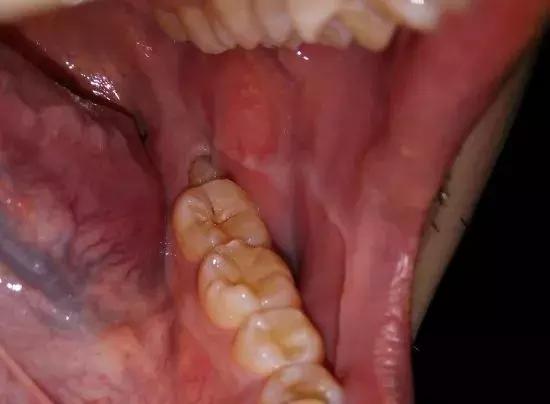

买了尽头刷就能做到每天清理歪头的智齿了吗,这就是大多数人嘴里智齿的清洁程度↓

2

智齿阻生,萌出不全

会引起局部肿胀疼痛

不是持续的胀痛,是那种反反复复红肿,特别磨人↓

你想着,等完全长出来就去拔,这一等又是一年多。

真相是,它真的就到这为止了,就露个尖儿↓